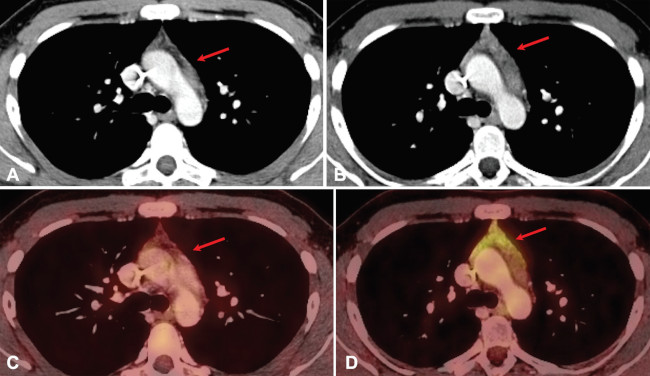

Aunque los dos tipos de hiperplasia tímica son imposibles de diferenciar mediante imágenes, la hiperplasia tímica generalmente puede distinguirse de procesos expansivos en base a ciertos hallazgos orientadores. La hiperplasia tímica generalmente se presenta como un aumento difuso y simétrico de volumen tímico, de contornos suaves, con densidad intercalada de grasa y de partes blandas, manteniendo los planos grasos de clivaje (►Fig. 2). En contraste con lo anterior, un tumor tímico puede demostrar una masa focal, contornos nodulares, heterogeneidad (que representa hemorragia o necrosis) y/o calcificaciones.7 Los valores SUVmáx de 18F-FDG en hiperplasia tímica se sitúan aproximadamente entre 2,0 y 2,8.2 Se puede emplear la imagen de RM por desplazamiento químico (chemical shift). Así, en la hiperplasia tímica, podemos observar una caída de señal en las imágenes fuera de fase respecto de las imágenes en fase, debido a la presencia de grasa microscópica en el timo hiperplásico (►Fig. 3).8